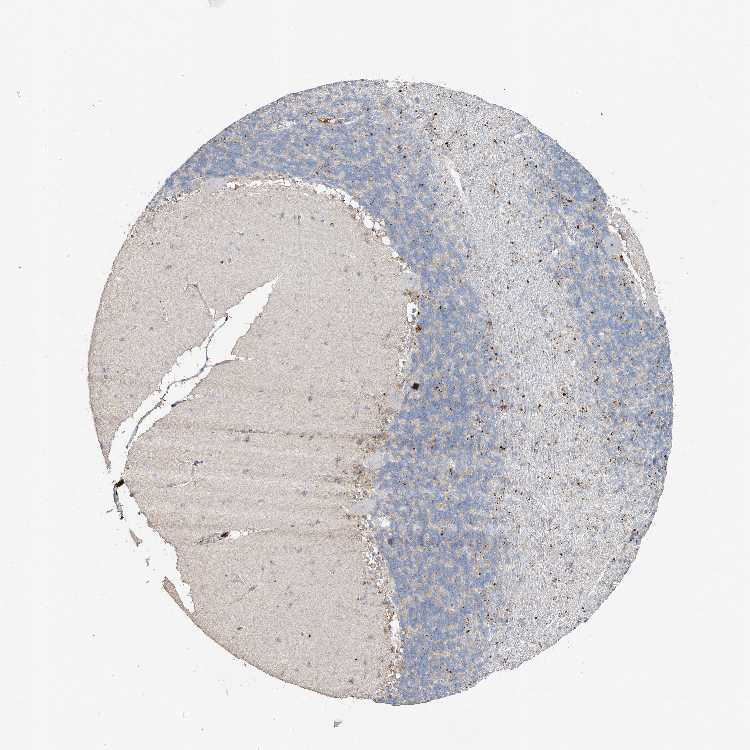

CEREBELLUM - Antibody stainingi

Antibody staining in the annotated cell types in the current human tissue is reported as not detected, low, medium, or high, based on conventional immunohistochemistry profiling in selected tissues. This score is based on the combination of the staining intensity and fraction of stained cells.

Each image is clickable and will lead to virtual microscopy that enables deeper exploration of all samples and also displays staining intensity scores, fraction scores and subcellular localization as well as patient and tissue information for each sample.

Antibody HPA014933

Purkinje cells Not detected

Cells in granular layer Not detected

Cells in molecular layer Not detected